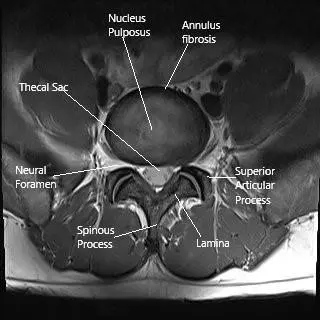

MRI of the lumbar spine in the axial section.

How the Body Part Normally Works? (Relevant Anatomy)

The spinal cord runs through the spinal canal, surrounded by protective layers called the meninges and the vertebrae. Nerves branch off from the spinal cord to transmit signals to the rest of the body.

When a tumor develops inside or near the spinal cord, it can compress these structures, leading to pain, numbness, weakness, and, in severe cases, loss of bowel or bladder control.